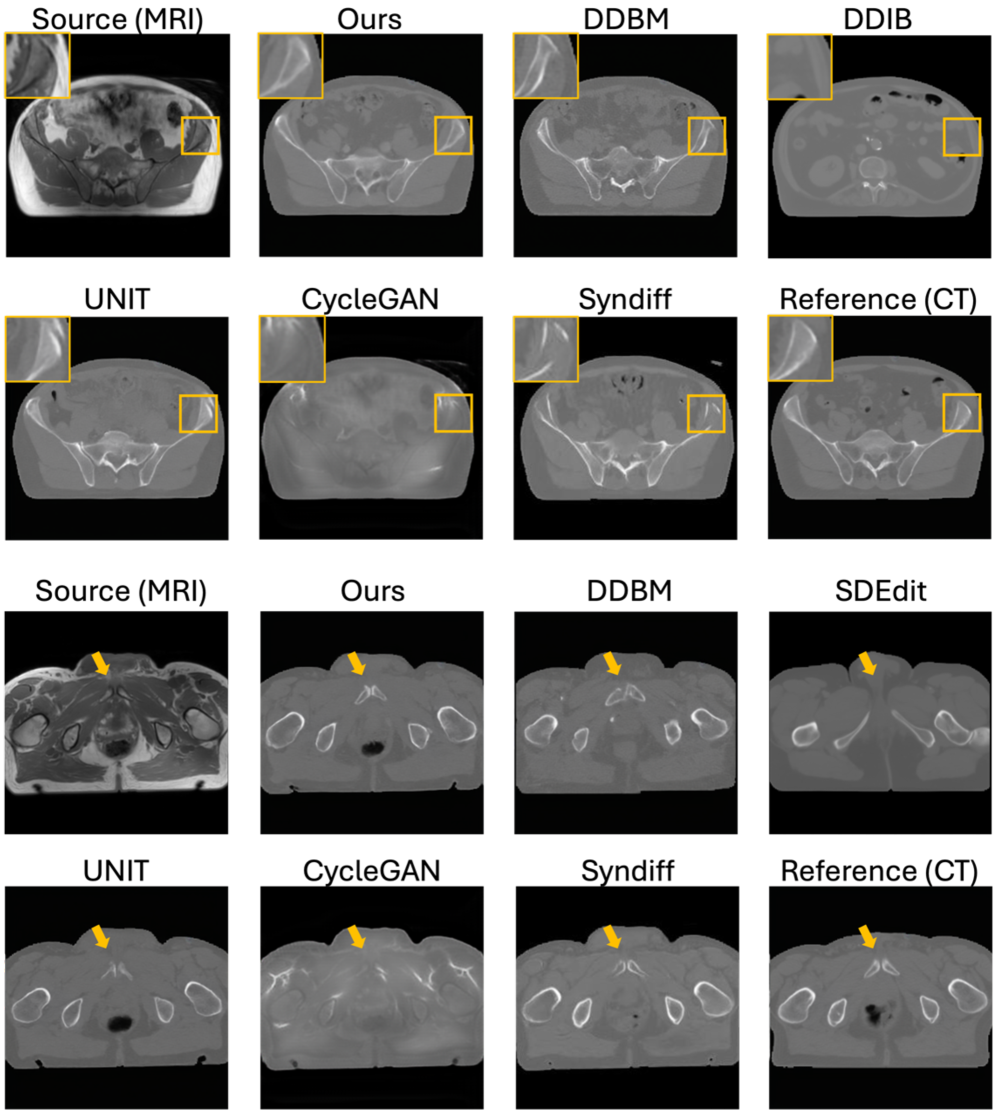

Refer to caption

Figure 4: Our SSB ensures anatomically consistent MRI\rightarrowCT translation across in-domain and out-of-domain scenarios. Segmentation masks are overlaid on MRI source images in OOD settings to provide structural reference, as paired CT ground truth is unavailable. They are not used during training or inference and serve only to illustrate anatomical fidelity without segmentation supervision.

We compare our method against representative baselines widely used in medical I2I translation, including GAN-based models CycleGAN Zhu et al. (2017) and UNIT Liu et al. (2017), zero-shot diffusion approaches SDEdit Meng et al. (2022) and DDIB Su et al. (2023), and the hybrid CycleGAN–diffusion framework SynDiff Özbey et al. (2023a). Since edge-based representations, such as Canny edges, are commonly used in MRI–CT translation—where diffusion models learn to reconstruct images from edge maps in a self-supervised manner Chen et al. (2024)—we additionally implement a DDBM variant using Canny edges. This comparison demonstrates that DINO-based embeddings capture richer geometric and semantic information than handcrafted edge filters. Fig. 4 and Table 1 present qualitative and quantitative results on in-domain and OOD MRI\rightarrowCT translation. Since no paired CT is available, we compute FID against CT scans from the training set and MS-SSIM between the input MRI and the synthesized CT as a proxy for structural similarity. We also provide qualitative results and segmentation overlays, with additional visuals in the Appendix. Our method shows stronger robustness to new MRI contrasts and achieves more accurate translations than SynDiff and DDBM, preserving geometry and modality realism.